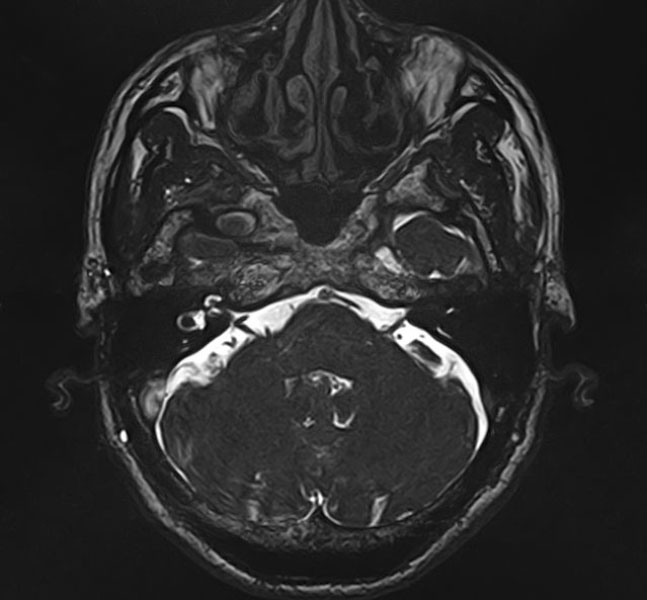

手術前

(MR1)